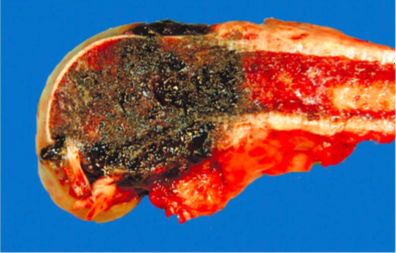

Give Name of Disease of the lungs of this 3 month old pig and describe lesions!

Name of Disease= Porcine Contagious Pleuropneumonia

Description= Focal areas of necrosis and hemorrhage in middle and caudal lung lobes